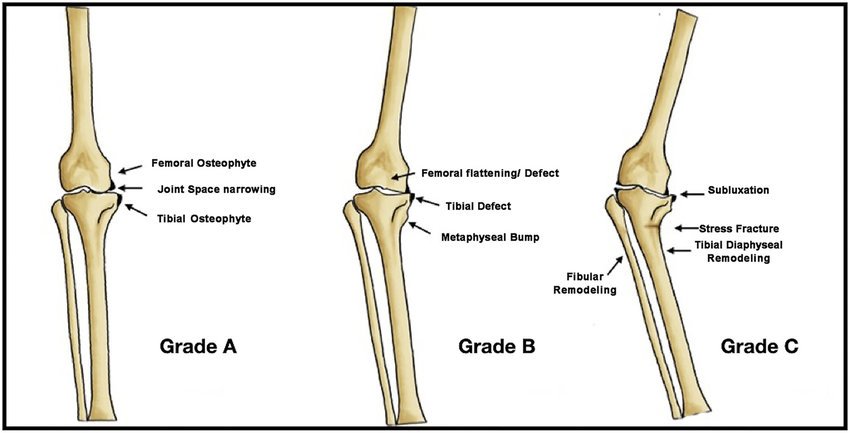

| Subluxation | Partial displacement of a joint | |

| Eburnation | Dense bone formed when cartilage is worn away. | ![]() |

| Exostosis | A bony out growth | ![]() |